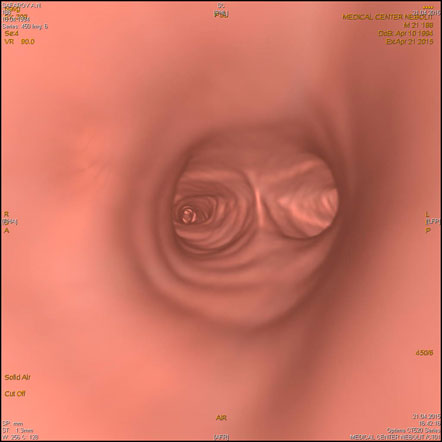

- Программа виртуальной эндоскопии-для просмотра трахеи, бронхов, толстого кишечника

МСКТ органов грудной клетки (легких и средостения).Рентген является базовым методом исследования грудной клетки. МСКТ применяется в выявлении стадии рака легкого, туберкулеза, определяет структуру патологических образований, таких как киста, солидный компонент, сосудистые, жидкостные и воздушные полости, подозрение на ТЭЛА.

С появлением МСКТ уходит в прошлое КТ с высоким разрешением для диагностики интерстициальных заболеваний легких. При использовании МСКТ можно дифференцировать диффузные интерстициальные процессы в легких альвеолит, бронхиолит, саркоидоз, канцироматоз и очаговые изменения.

Астма и хронический бронхит диагностируются клинически. Половина больных с хроническим бронхитом имеют нормальную картину при рентгенографии. При МСКТ у пациентов можно выявить признаки обструкции-участки вздутия легочной ткани обусловленные закупоркой мелких бронхов, участки гиповентиляции за счет отека слизистой, эмфизематозные буллы, дисковидные ателектазы, бронхоэктазы.